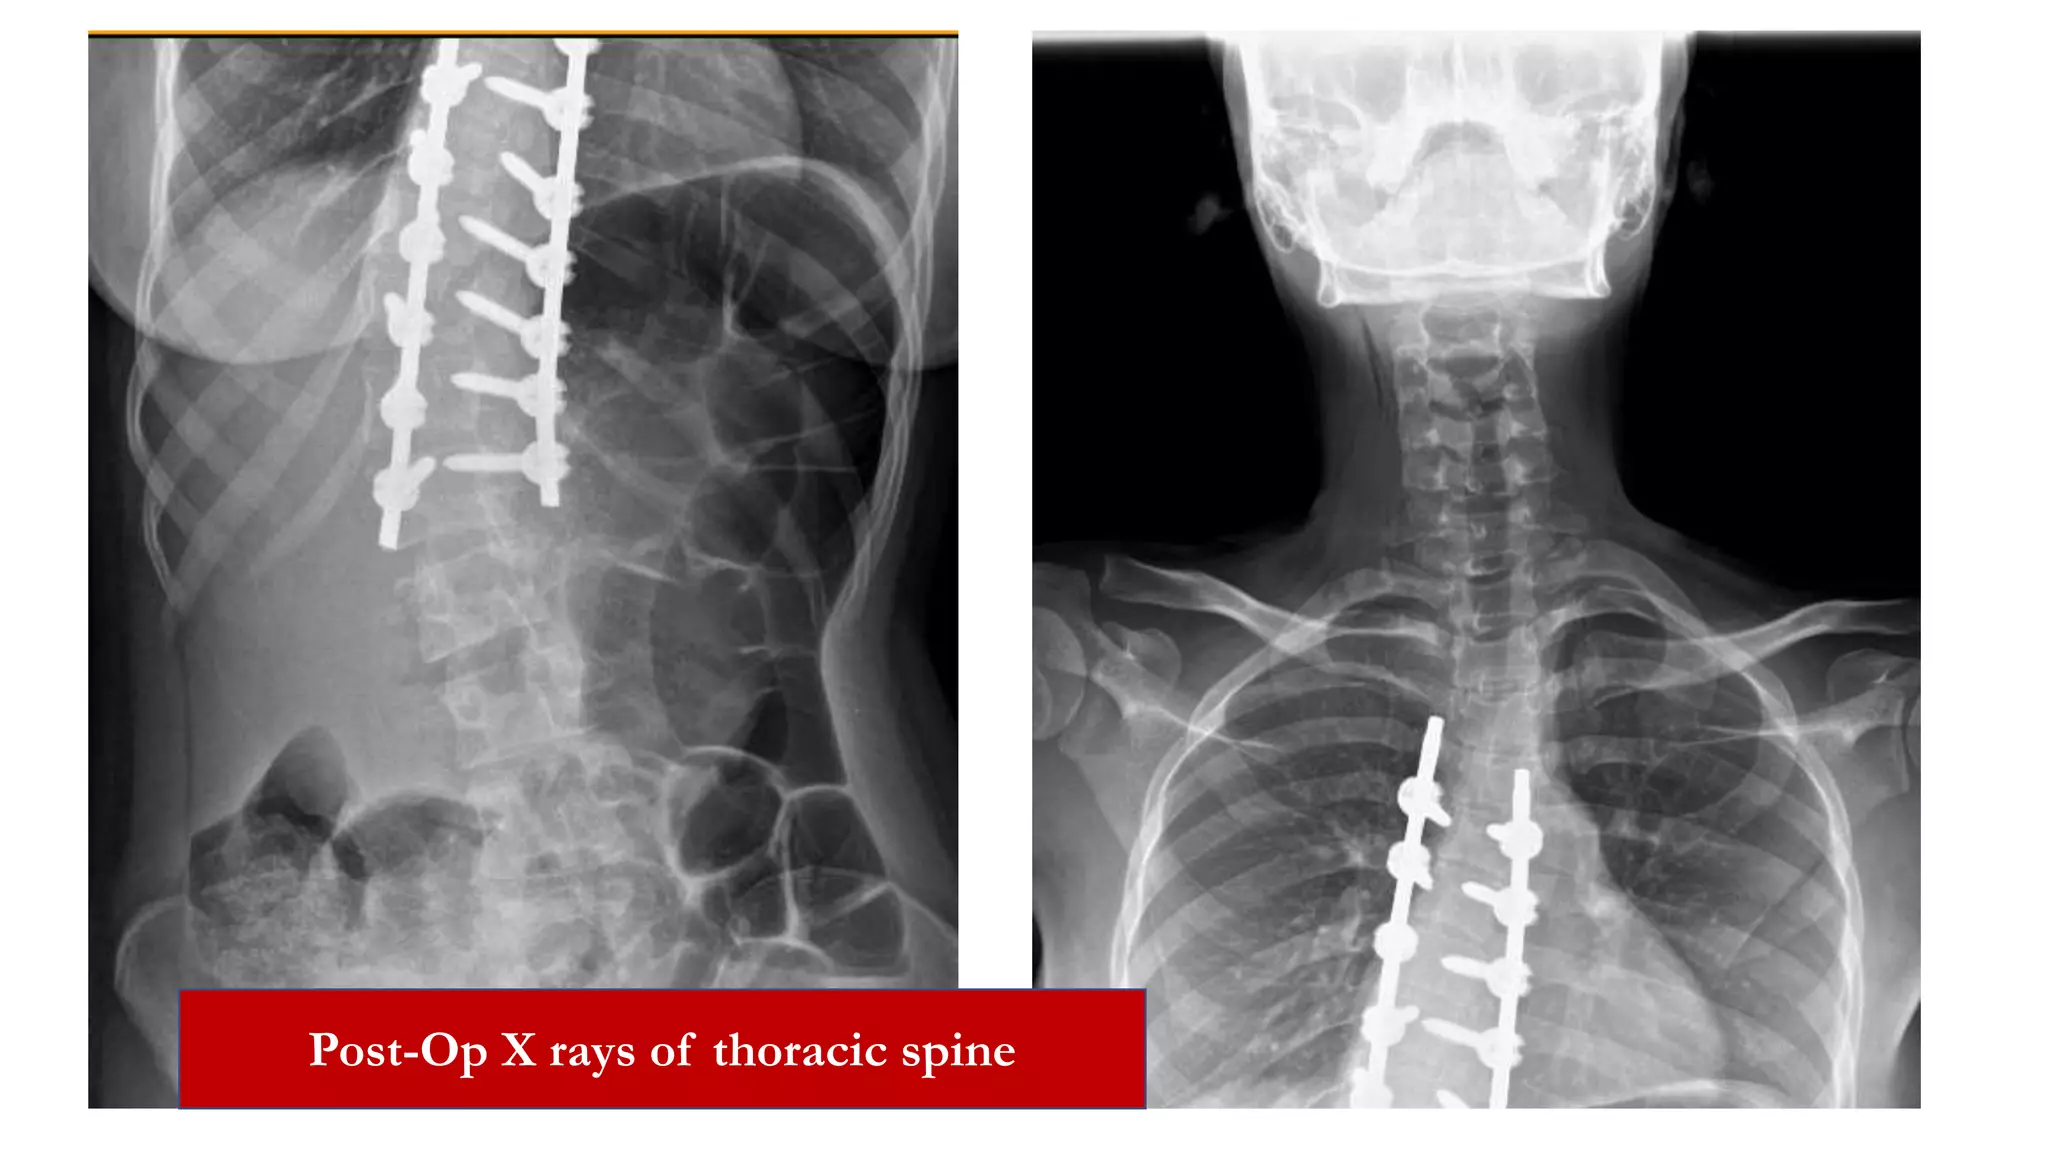

Post-Op X rays of thoracic spine

Follow up

• Her shoulders were at same level, pelvis was squared and she was

standing in erect posture and walking with normal gait.

• Post op X-ray showed correction of thoracic deformity with

residual deformity of 25 degrees and her shoulders and pelvis were

at same level.

• No neurological deficits.

• Doing well; 2 years of follow up.